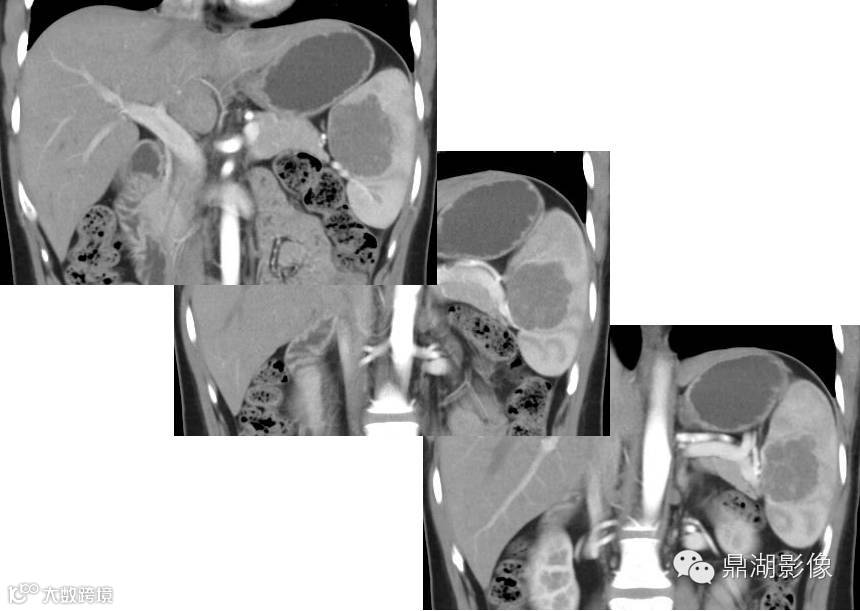

冠状位

增强扫描特点:动脉期肿块边缘点状及线条样强化,门脉期及延迟期强化渐向中部充填,与脾脏几成等密度,肿块显示渐缩小。是不是让你觉得很简单,但是答案是:

手术所见:脾脏颜色红润,质韧,与周围无粘连,脾门处可触及大小约4×4cm肿块,质硬